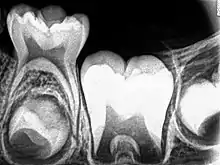

_showing_Deciduous(Milky_or_Primary)_Tooth_75_and_developing_crown_of_Permanent_or_Secondary_Teeth_35%252C_36_and_37.jpg.webp)

Although tooth eruption occurs at different times for different people, a general eruption timeline exists. Typically, humans have 20 primary (baby) teeth and 32 permanent teeth.[44] Tooth eruption has three stages. The first, known as deciduous dentition stage, occurs when only primary teeth are visible. Once the first permanent tooth erupts into the mouth, the teeth are in the mixed (or transitional) dentition. After the last primary tooth falls out of the mouth—a process known as exfoliation—the teeth are in the permanent dentition.

Primary dentition starts on the arrival of the mandibular central incisors, usually at eight months, and lasts until the first permanent molars appear in the mouth, usually at six years.[45] The primary teeth typically erupt in the following order: (1) central incisor, (2) lateral incisor, (3) first molar, (4) canine, and (5) second molar.[46] As a general rule, four teeth erupt for every six months of life, mandibular teeth erupt before maxillary teeth, and teeth erupt sooner in females than males.[47] During primary dentition, the tooth buds of permanent teeth develop below the primary teeth, close to the palate or tongue.

Mixed dentition starts when the first permanent molar appears in the mouth, usually at six years, and lasts until the last primary tooth is lost, usually at eleven or twelve years.[48] Permanent teeth in the maxilla erupt in a different order from permanent teeth on the mandible. Maxillary teeth erupt in the following order: (1) first molar (2) central incisor, (3) lateral incisor, (4) first premolar, (5) second premolar, (6) canine, (7) second molar, and (8) third molar. Mandibular teeth erupt in the following order: (1) first molar (2) central incisor, (3) lateral incisor, (4) canine, (5) first premolar, (6) second premolar, (7) second molar, and (8) third molar. Since there are no premolars in the primary dentition, the primary molars are replaced by permanent premolars.[49] If any primary teeth are lost before permanent teeth are ready to replace them, some posterior teeth may drift forward and cause space to be lost in the mouth.[50] This may cause crowding and/or misplacement once the permanent teeth erupt, which is usually referred to as malocclusion. Orthodontics may be required in such circumstances for an individual to achieve a straight set of teeth.